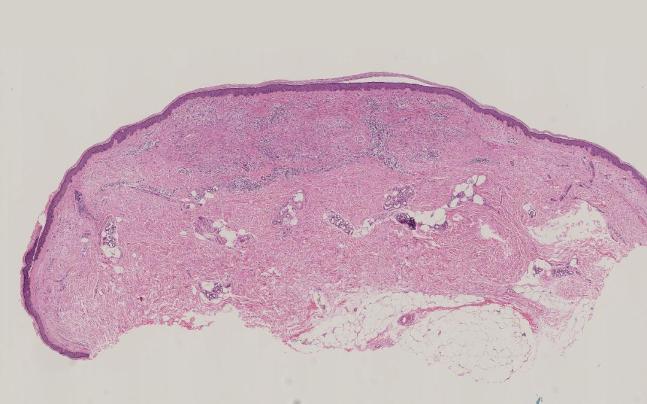

4)皮肤活检:

病理检查:表皮未见明显异常,淋巴、组织细胞浸润呈栅栏样排列伴胶原渐进性坏死,可见少数多核组织巨细胞,结合临床可符合环状肉芽肿。

c. 组织病理学:

GA的特征性组织病理学表现为淋巴组织细胞浸润、胶原变性和黏蛋白沉积,这些表现通常呈栅栏样或间质模式。可通过阿尔新蓝突出显示黏蛋白沉积。局限型和泛发型GA均可见栅栏样和间质模式,斑片型GA通常为间质模式。

间质模式:特征为真皮中上层组织细胞嵌入嗜碱性黏蛋白并浸润于胶原束间。胶原纤维出现不完全变性。

栅栏样模式:特征为真皮中上层淋巴组织细胞炎性浸润,而炎性浸润呈栅栏样包绕胶原及弹性蛋白变性区域。胶原变性区域表现为嗜酸性纤维物质被嗜碱性黏蛋白沉积物所分隔。也可能存在嗜酸性粒细胞。